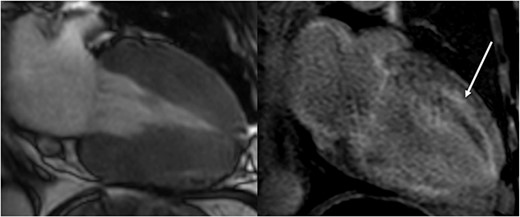

A subsequent operation with decompression via interlaminar fenestration led to clinical improvement without complete resolution of the symptoms. The histology obtained showed increased amyloid deposition in the ligamenta flava. In parallel, an increasing cardiomyopathy developed, with left ventricular hypertrophy and reduced contractility confirmed by ultrasound and cardiac MRI (Fig. 3). Additional 2,3-dicarboxypropane-1, 1-diphosphonate (DPD) scintigraphy led to a pathognomonic storage in the area of the heart muscle (Fig. 4) and the thigh muscles. Over the course of the disease, the patient experienced significant weight loss and recurrent, sometimes bloody diarrhoea. Colonoscopy with sampling of the rectum confirmed the presence of an amyloid-associated enteropathy. The patient also developed stage 2 renal insufficiency.

Cardiac MRI (2-chamber view) shows marked hypertrophy of the ventricular musculature on the left in the onset of systole. On the right, there is a clear late enhancement after administration of gadolinium diethylenetriaminepentaacetic acid (DTPA) (arrow).